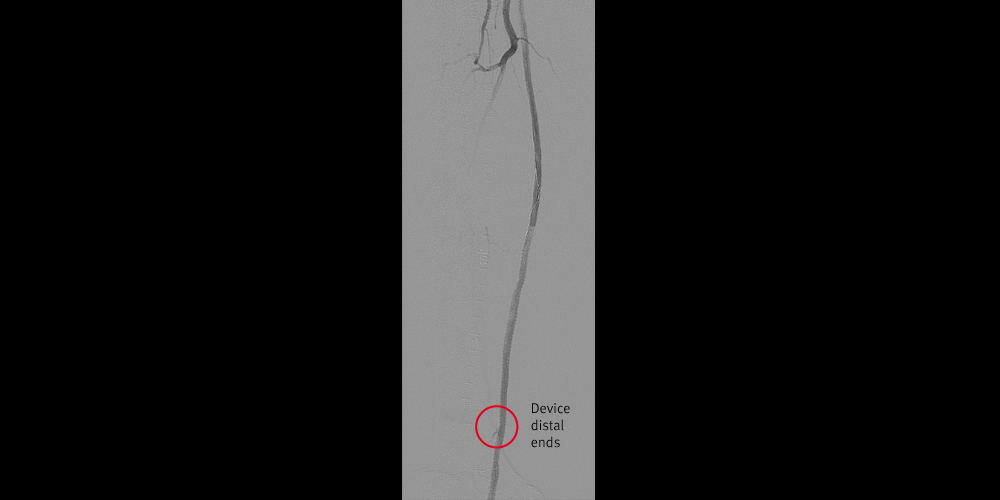

Result

- Proximal device placed successfully at the ostium of the SFA

- Correct sizing with 5 mm device

- Excellent radiographic result

- Patient’s ulcer healed after intervention

- Stent graft patent through most recent available follow-up over 18 months post-procedure

Case Takeaways

- Limb salvage by endoluminal bypass in Rutherford 6 limb

- While initial PTA demonstrated a good result, diabetic patients have diffuse disease and the arteriogram understates the plaque burden in these patients

- Cover healthy-to-healthy to the extent possible